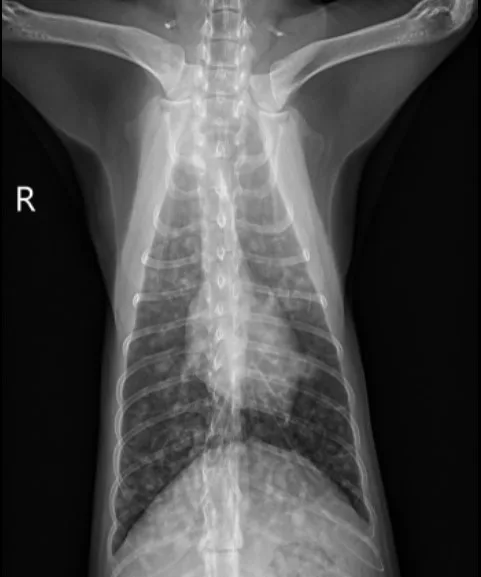

Butorphanol (0.2 mg/kg IV) was administered for sedation to obtain 3-view thoracic radiographs (left lateral, right lateral, ventrodorsal). Results revealed diffuse pulmonary nodular changes with an underlying bronchointerstitial pattern (Figure 1). Fungal pneumonia, parasitic pneumonia, neoplasia, and eosinophilic inflammatory disease were the most likely differentials for this pattern.

A

FIGURE 1 Left lateral (A), right lateral (B), and ventrodorsal (C) thoracic radiographs at the time of initial diagnosis. Diffuse pulmonary nodular changes with an underlying bronchointerstitial pattern can be seen.